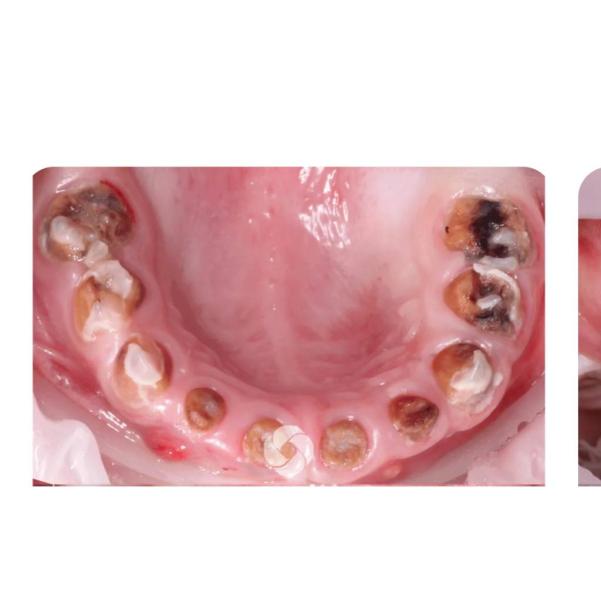

Девочки поделитесь опытом. У нас такая ситуация. На 2 фото👉 примерное состояние зубов моей младшей дочери (!!! впечетлительным не смотреть). У нас диагноз был гипоплазия эмали(поэтому верхние зубы к 2 годам расстворились) остались только "пеньки".Сейчас настал период, когда начинают выходить " прстоянные" зубы, а эти "пеньки" от молочных мешают им. Я понимаю, что их нужно удалять. Перелопатила интернет, все делают под наркозом, а я не хочу. Максимум согласна на седацию Поделитесь в каких клиниках Краснодара, Вы это делали? Буду очень благодарна!!!